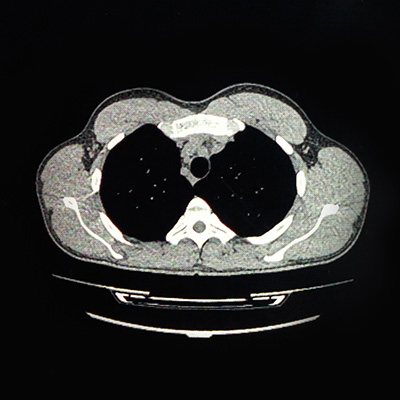

- After birth: A chest X-ray or CT scan may be used if symptoms develop or if an abnormality is suspected.